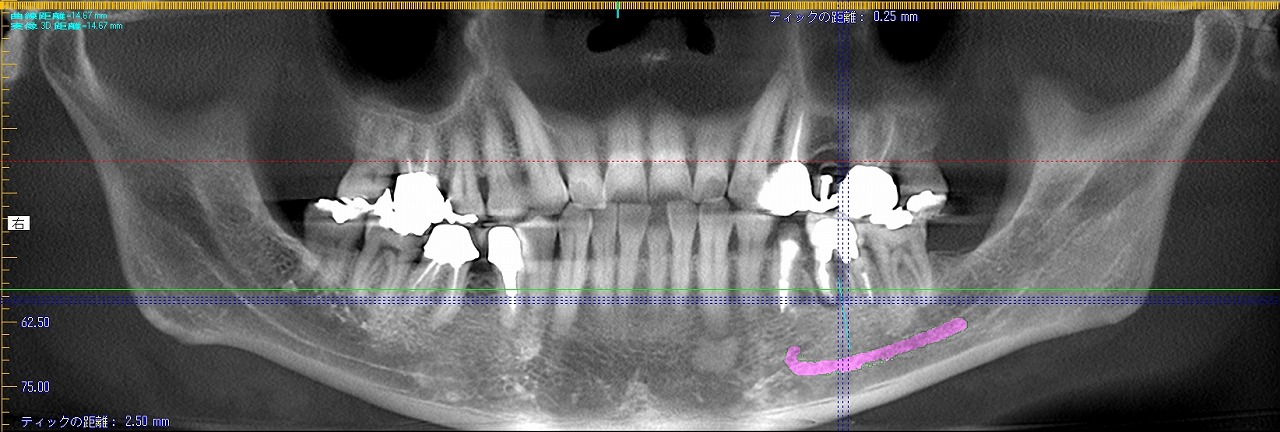

左下6番、破折によりインプラント即時埋入|お知らせ |広島市安佐南区の歯科医院 左下6番、破折によりインプラント即時埋入 トップ お知らせ・ブログ お知らせ 左下6番、破折によりインプラント即時埋入 左下6番、破折によりインプラント即時埋入 近心根に器具の破折が見て取れます 症状もありかぶせを外して根の治療をしていきます 被せをを外していきました これより根の治療をしていきます 土台を外していきます この歯は割れていました 抜歯をさせていただきました 補填材を入れ、インプラント埋入終了 CTデータになります 術前と述語になります Web診療予約 初めての方へ 選ばれ続ける理由 院内設備について 歯が痛いしみる一般歯科 歯がぐらぐらする歯周病 健康な歯を保ちたい予防歯科 子供の虫歯予防をしたい小児歯科 銀歯をセラミックに審美歯科 白い歯を目指しませんか?ホワイトニング 矯正専門医がいるので安心矯正歯科 抜けた歯を補いたいインプラント・入れ歯 医院案内 スタッフ紹介 メリィハウス歯科クリニックオフィシャルホームページ ラベンダー歯科クリニックオフィシャルホームページ お知らせ・ブログ ホーム 診療科目 一般歯科 歯周病治療 予防治療 小児歯科 審美治療 ホワイトニング 矯正歯科 入れ歯・インプラント マウスピース矯正 初めての方へ 院長・スタッフ 設備紹介 医院案内・アクセス メニューを閉じる